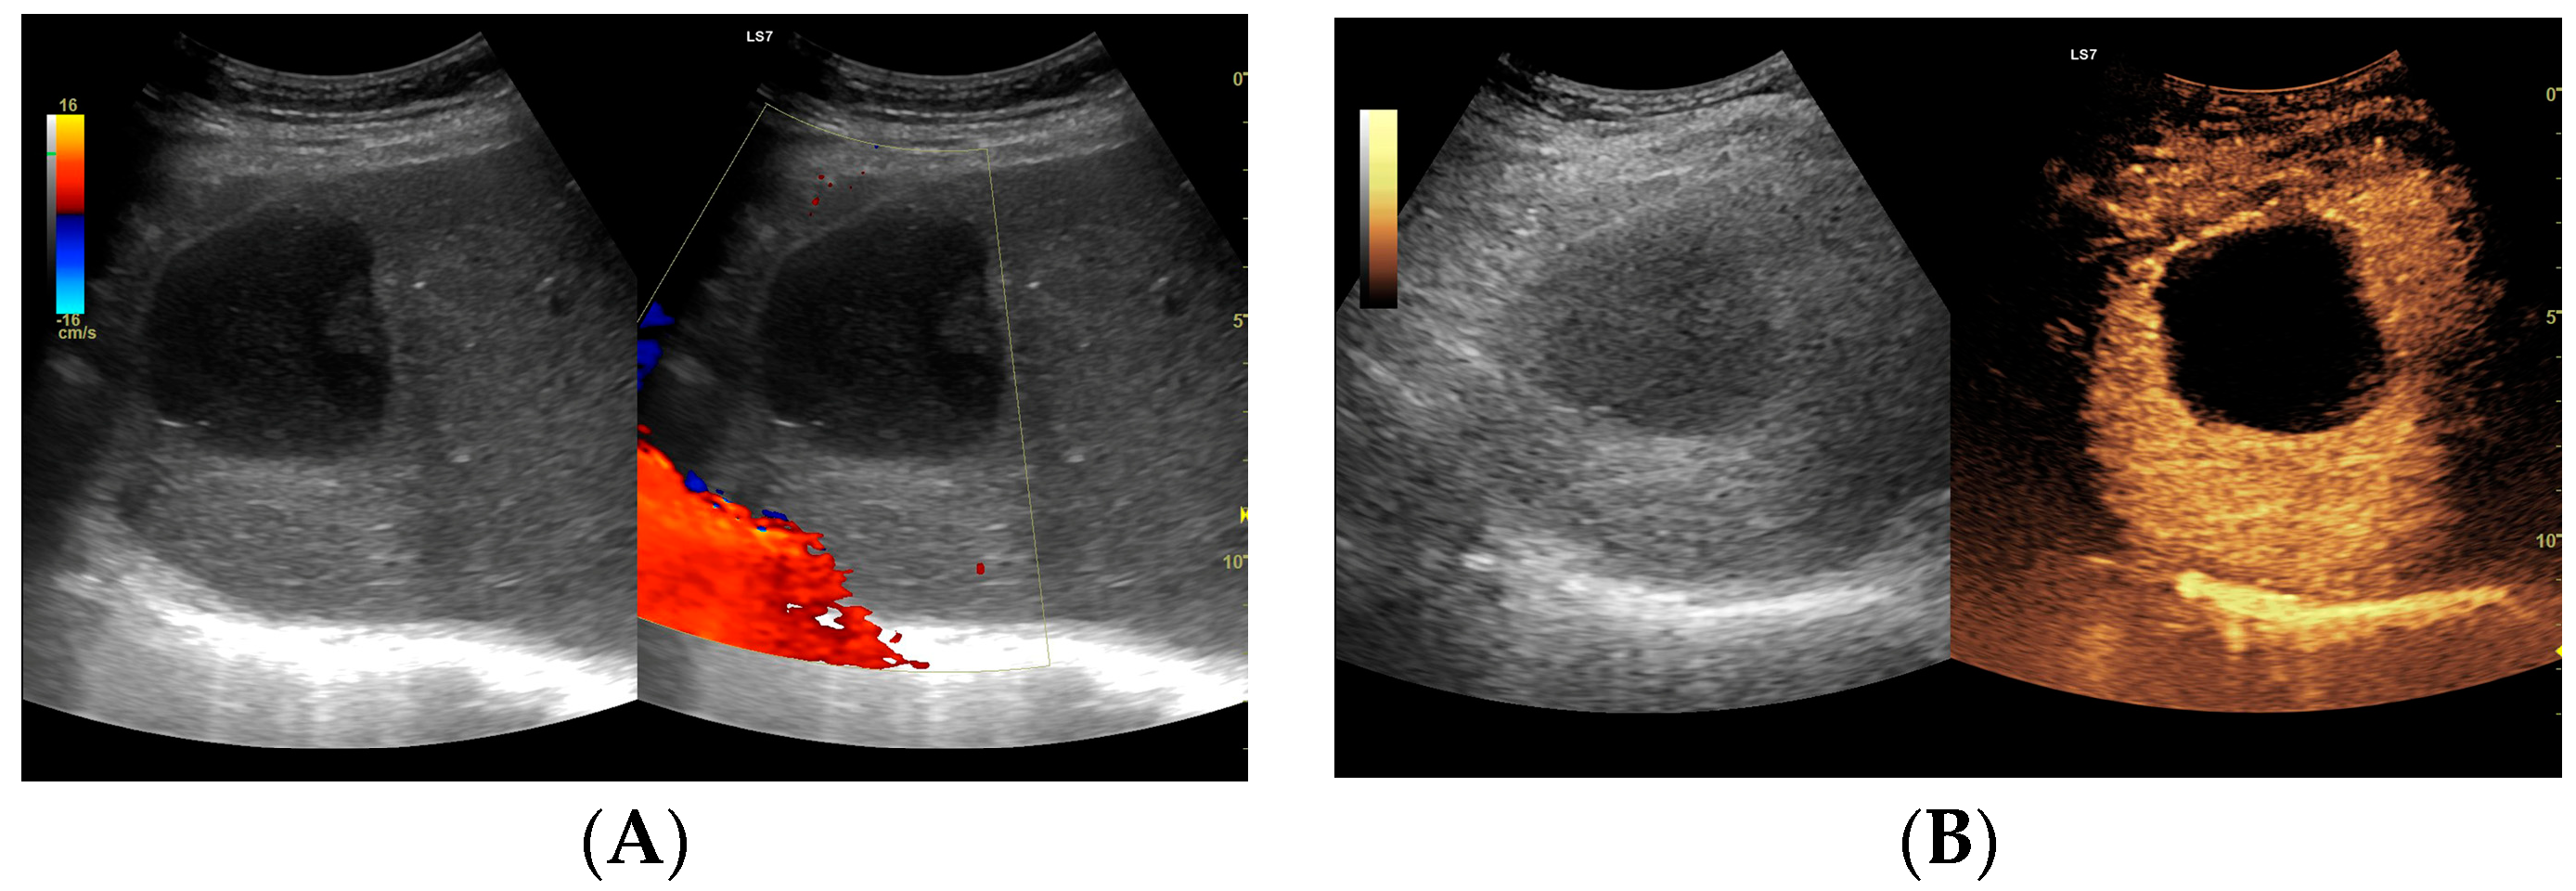

Figure 8.

Focal liver lesion diagnosed as a type III abscess. (A) Post-contrast image on CT. (B) B-mode ultrasound: the fluid component of the lesion is difficult to define. (C) CEUS: the fluid component of the lesion is visible, and the patient is qualified for percutaneous drainage. (D) Post-contrast image on CT: Follow-up examination one week after placement of drains shows a visible reduction in the fluid component. The lesion is transitioning from type III to type II, with a visible “honeycomb” sign. (E) B-mode ultrasound: the fluid component of the lesion remains challenging to define. (F) CEUS: the fluid component of the lesion is visible, indicating regression from stage III to II. (G) Post-contrast image on CT: follow-up examination performed 1.5 months after placement of percutaneous drainage reveals a visible residual lesion. (H) B-mode ultrasound: a residual lesion is visible. (I) CEUS: the residual lesion shows the fluid component to be completely invisible, with a connective tissue scar present.